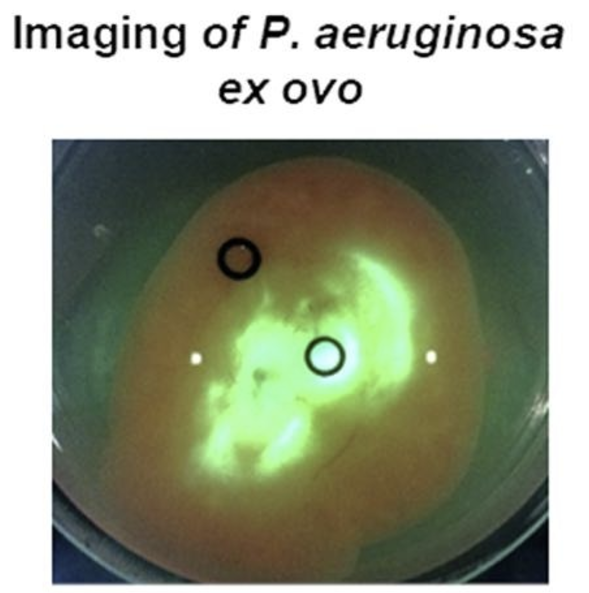

A shell-less hen’s egg test as infection model to determine the biocompatibility and antimicrobial efficacy of drugs and drug formulations against Pseudomonas aeruginosa

Warncke P et al. Int. J. Pharmaceutics 2020